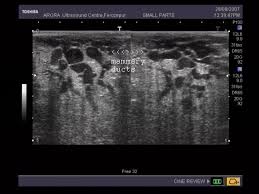

What Does Inflammatory Breast Cancer Look Like On Ultrasound / Benign And Malignant Characteristics Of Breast Lesions At Ultrasound Radiology Reference Article Radiopaedia Org : Ultrasound is useful for looking at some breast changes, such as lumps (especially those that can be felt but not seen on a mammogram) or changes in women with dense breast tissue.. Unlike typical breast cancer, ibc usually cannot be detected by a mammogram or ultrasound. What does breast cancer look like on a mammogram? Inflammatory carcinoma of the breast, also referred to as inflammatory breast cancer, is a relatively uncommon but aggressive form of invasive breast carcinoma with a characteristic clinical presentation and unique radiographic appearances. I need some knowledge about ibc. My last breast ultrasound was december.

Early warning signs of inflammatory breast cancer along with images of inflammatory breast cancer are mentioned below. Does this look like inflammatory breast cancer? Unlike typical breast cancer, ibc usually cannot be detected by a mammogram or ultrasound. Ultrasounds are useful for detecting signs of breast cancer even after a mammogram comes back negative. Googled and freaking out about ibc. The usual cause of inflammatory breast symptoms is breast mastitis or duct ectasia. The breast tissue deflects these waves causing echoes, which a computer uses to paint a picture of what's going on inside the breast tissue (no radiation is involved). In view of those symptoms often occur, and errors in diagnosis of patients treated for inflammatory diseases, that happen to be named and are known as these forms breast cancer.

These tubes, which are hollow, allow lymph fluid to drain out of the breast. The problem is that inflammatory breast cancer can look very much like mastitis early on, and is often diagnosed only after a woman has been treated first for mastitis (often with no improvement in symptoms). Kathleen ruddy inflammatory breast cancer accounts for approximately 5% of all cases of invasive breast cancer in the united states. Inflammatory breast cancer is often misdiagnosed because it is so rare, and is difficult to treat because it is particularly aggressive. A small red spot that looks very much like an insect bite or rash can be an early sign of ibc. Because ibc grows quickly, it is usually found at a locally advanced stage, meaning that cancer cells have spread into nearby breast tissue or lymph nodes. Googled and freaking out about ibc. The woman who has inflammatory breast cancer has breast cancer that's red and inflamed, with an angry look to the breast cancer, he says. Online says it develops suddenly. However, these signs and symptoms are most often associated with benign breast conditions. Inflammatory breast cancer (ibc) is rare, making up about 2 to 4 percent of breast cancer cases. Other ultrasound findings that suggest breast cancer include: The breast tissue deflects these waves causing echoes, which a computer uses to paint a picture of what's going on inside the breast tissue (no radiation is involved).